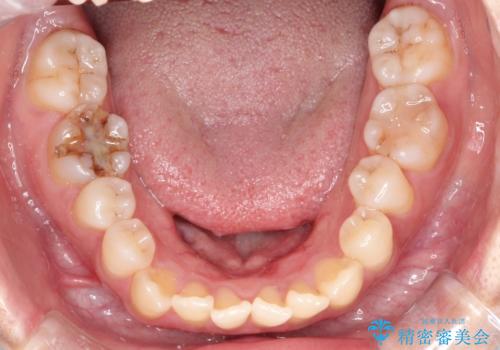

【開咬】笑った時の見た目を改善したい。

- 重度の開咬でしたがインビザラインで適切に治療計画を立て、きれいに仕上がりました。